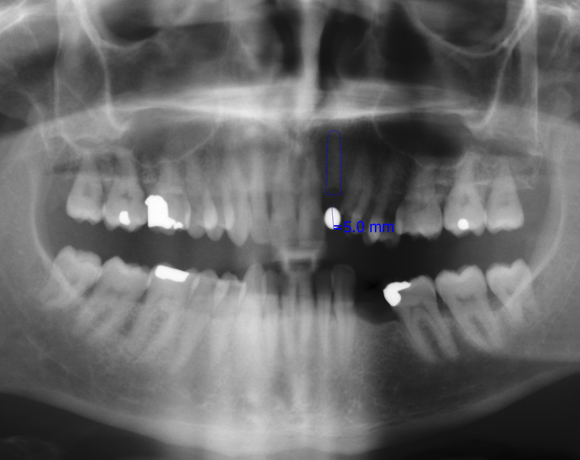

Zeramex Implantat auf Zahn12

Ein Projekt aus dem Jahr 2011

Bei diesem Patienten wurde der nichterhaltungswürdige Zahn 12 mit einem Zerameximplantat versorgt. Nach der Einheilphase wurden auch die Zähne 14 und 13 mit e.max Kronen versorgt